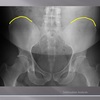

AP LUMBOPELVIC LANDMARKS A-P lumbopelvic view

femur heads

110

A-P lumbopelvic view

superior iliac crests

111

lateral iliac crests

112

ischial tuberosities

113

s2 tubercle

114

pubic/pubic symphysis

115

sacral grooves

116

lateral aspect of sacrum

117

medial aspect of ilium

118

obturator foramen

119

spinous processes

120

supeiror endplate tips

121

lumbar pedicle shadow